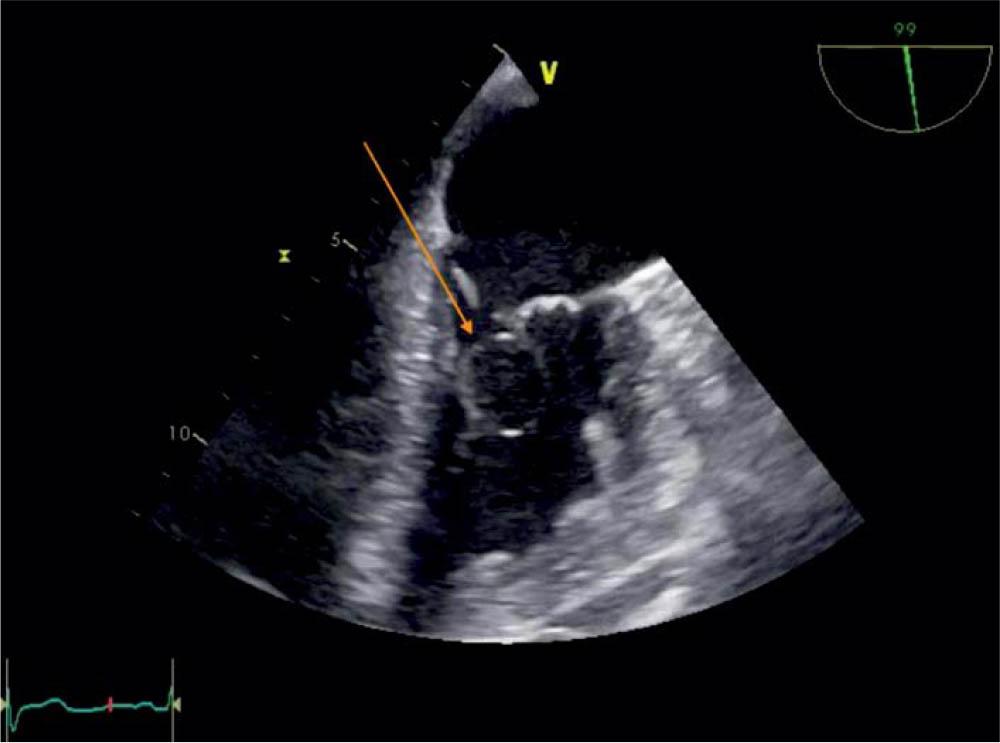

Figure 3

TEE 99 degrees, visualization of the blood cyst (arrow) attached to the MV.